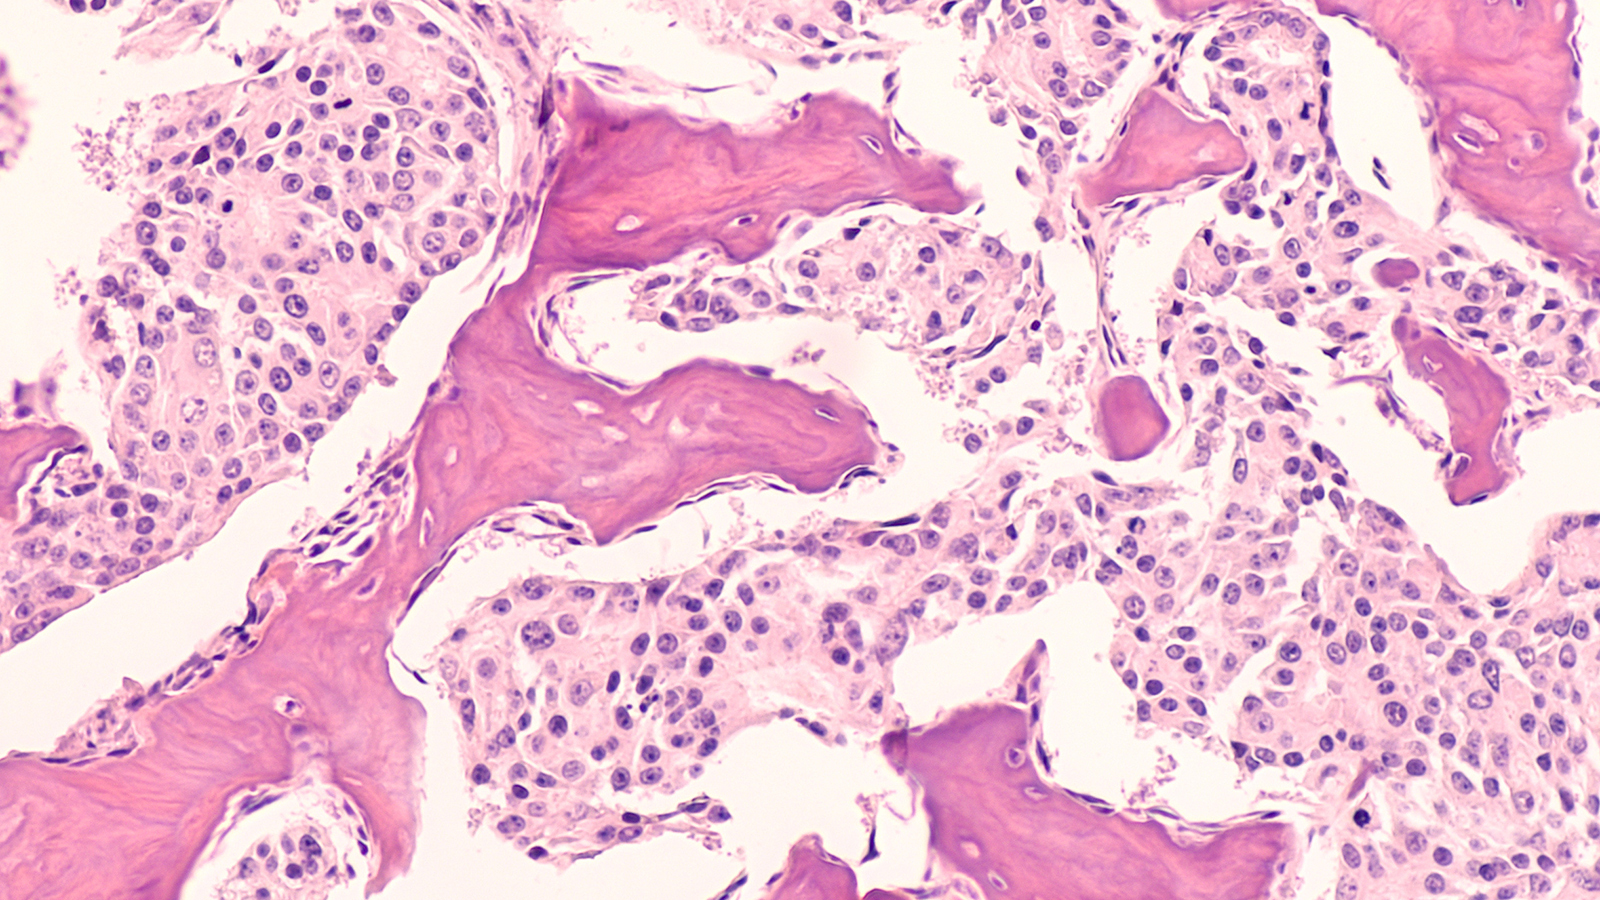

The status quo: Radiation therapy is a common cancer treatment that uses high doses of radiation to kill or slow the growth of cancer cells. Usually, this is done by aiming a beam of radiation directly at a tumor for a few minutes. This part of the process is painless, like getting an X-ray.

The challenge: By shrinking a tumor, radiation therapy can not only fight cancer, but also potentially relieve patients’ pain or other symptoms caused by it. But the beam of radiation can damage healthy tissue near the tumor, too, causing pain and other side effects.

It delivers a dose of radiation that’s over 300 times higher than traditional radiation therapy in just a fraction of a second. This induces something called the “FLASH effect” — a not-entirely-understood phenomenon in which the radiation still attacks the tumor, but doesn’t harm surrounding tissue.